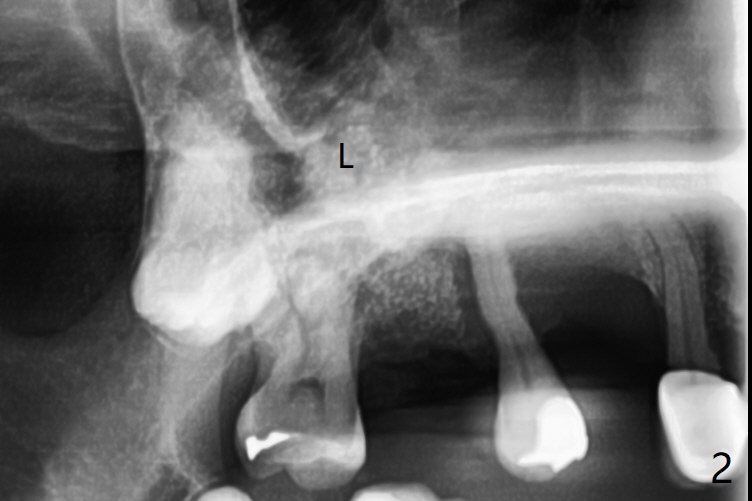

Since the tooth #3 has severe chronic periodontitis with 1 mm sinus floor (Fig.1 *), socket preservation may be not secure (B) in spite of using Cytoplast and PTFE suture. Prior to the bone graft, the sinus floor is lifted easily with Magic Sinus Lifter (IBS America) with Ossogen (mineralized cortical/cancellous (30%/70%) allograft, Fig.1,2 L). Periodontal dressing remains in place because of the neighboring teeth 1 week postop (Fig.3 D). Cytoplast remains in place after dislodgement of the periodontal dressing 2 weeks postop (Fig.4). Cytoplast dislodges 3 weeks postop (Fig.5). Socket preservation is not as secure as immediate implant in term of bone graft retention. What else can be done to prevent bone graft loss?